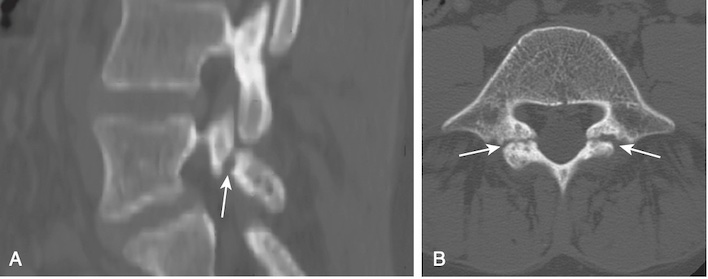

Chụp CT

- Chụp CT với khả năng quan sát xương rất tốt hiện được xem là thăm dò tốt nhất để quan sát trực tiếp các khiếm khuyết về xương của đoạn eo (Hình 4).

- Với trẻ em, chụp cộng hưởng từ (MRI) được xem là thăm dò hình ảnh đầu tiên, vì nó thể hiện mức độ thống nhất cao với SPECT / CT trong chẩn đoán hở eo ở trẻ vị thành niên mà không có nguy cơ chiếu xạ.

- Dấu hiệu: hình ảnh MRI đứng dọc với kỹ thuật bão hoà mỡ có thể xác định phù tủy xương biểu hiện phản ứng với stress ở phần eo trước khi gãy xương, và do đó trước khi có bất thường trên CT hoặc X quang.

- Khiếm khuyết gãy xương thường được ghi nhận là thiếu sự liên tục của xương giữa mỏm khớp trên và mỏm khớp dưới trên hình ảnh T1 đứng dọc (Hình 6).